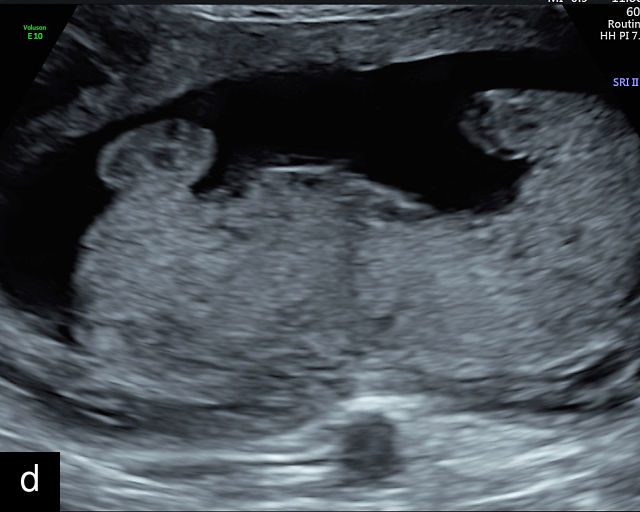

Normal ultrasound appearance of the placenta

Placental characteristics by trimester: thickness, echogenicity and location

In the early first trimester, trophoblastic tissue appears as an echogenic ring encircling the gestational sac (Figure 1a). By the late first trimester, the placenta becomes recognizable as a distinct structure on ultrasound (Figure 1b). Initially, it presents as a homogeneous echogenic mass (Figure 1b–d) but undergoes progressive differentiation, becoming more heterogeneous as pregnancy advances from the second to third trimester (Figure 1e–g). By the third trimester, cotyledons become discernible, and in the late third trimester, calcifications frequently appear basally and around the cotyledons (Figure 1g).

1

Ultrasound images of development of the placenta (P/p). (a) Trophoblastic tissue appearing as an echogenic ring surrounding the gestational sac at 6 weeks' gestation. (b) Placenta at 12 weeks has become a discrete, uniformly echogenic mass. (c) Placenta at 17 weeks. (d) Placenta at 20 weeks. (e) Placenta at 27 weeks. (f) Placenta at 33 weeks. Increasingly, differentiation and heterogeneous appearance is seen, with demarcation of the cotyledons. Basal calcifications are beginning to appear. (g) Placenta at 40 weeks, showing a distinctly heterogeneous appearance, with clear demarcation of the cotyledons and presence of calcifications.